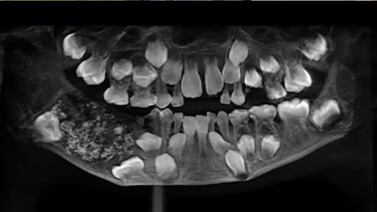

Una cirugía maxilofacial permitió descubrir cientos de miniestructuras dentales dentro de un tumor alojado en la mandíbula de un niño